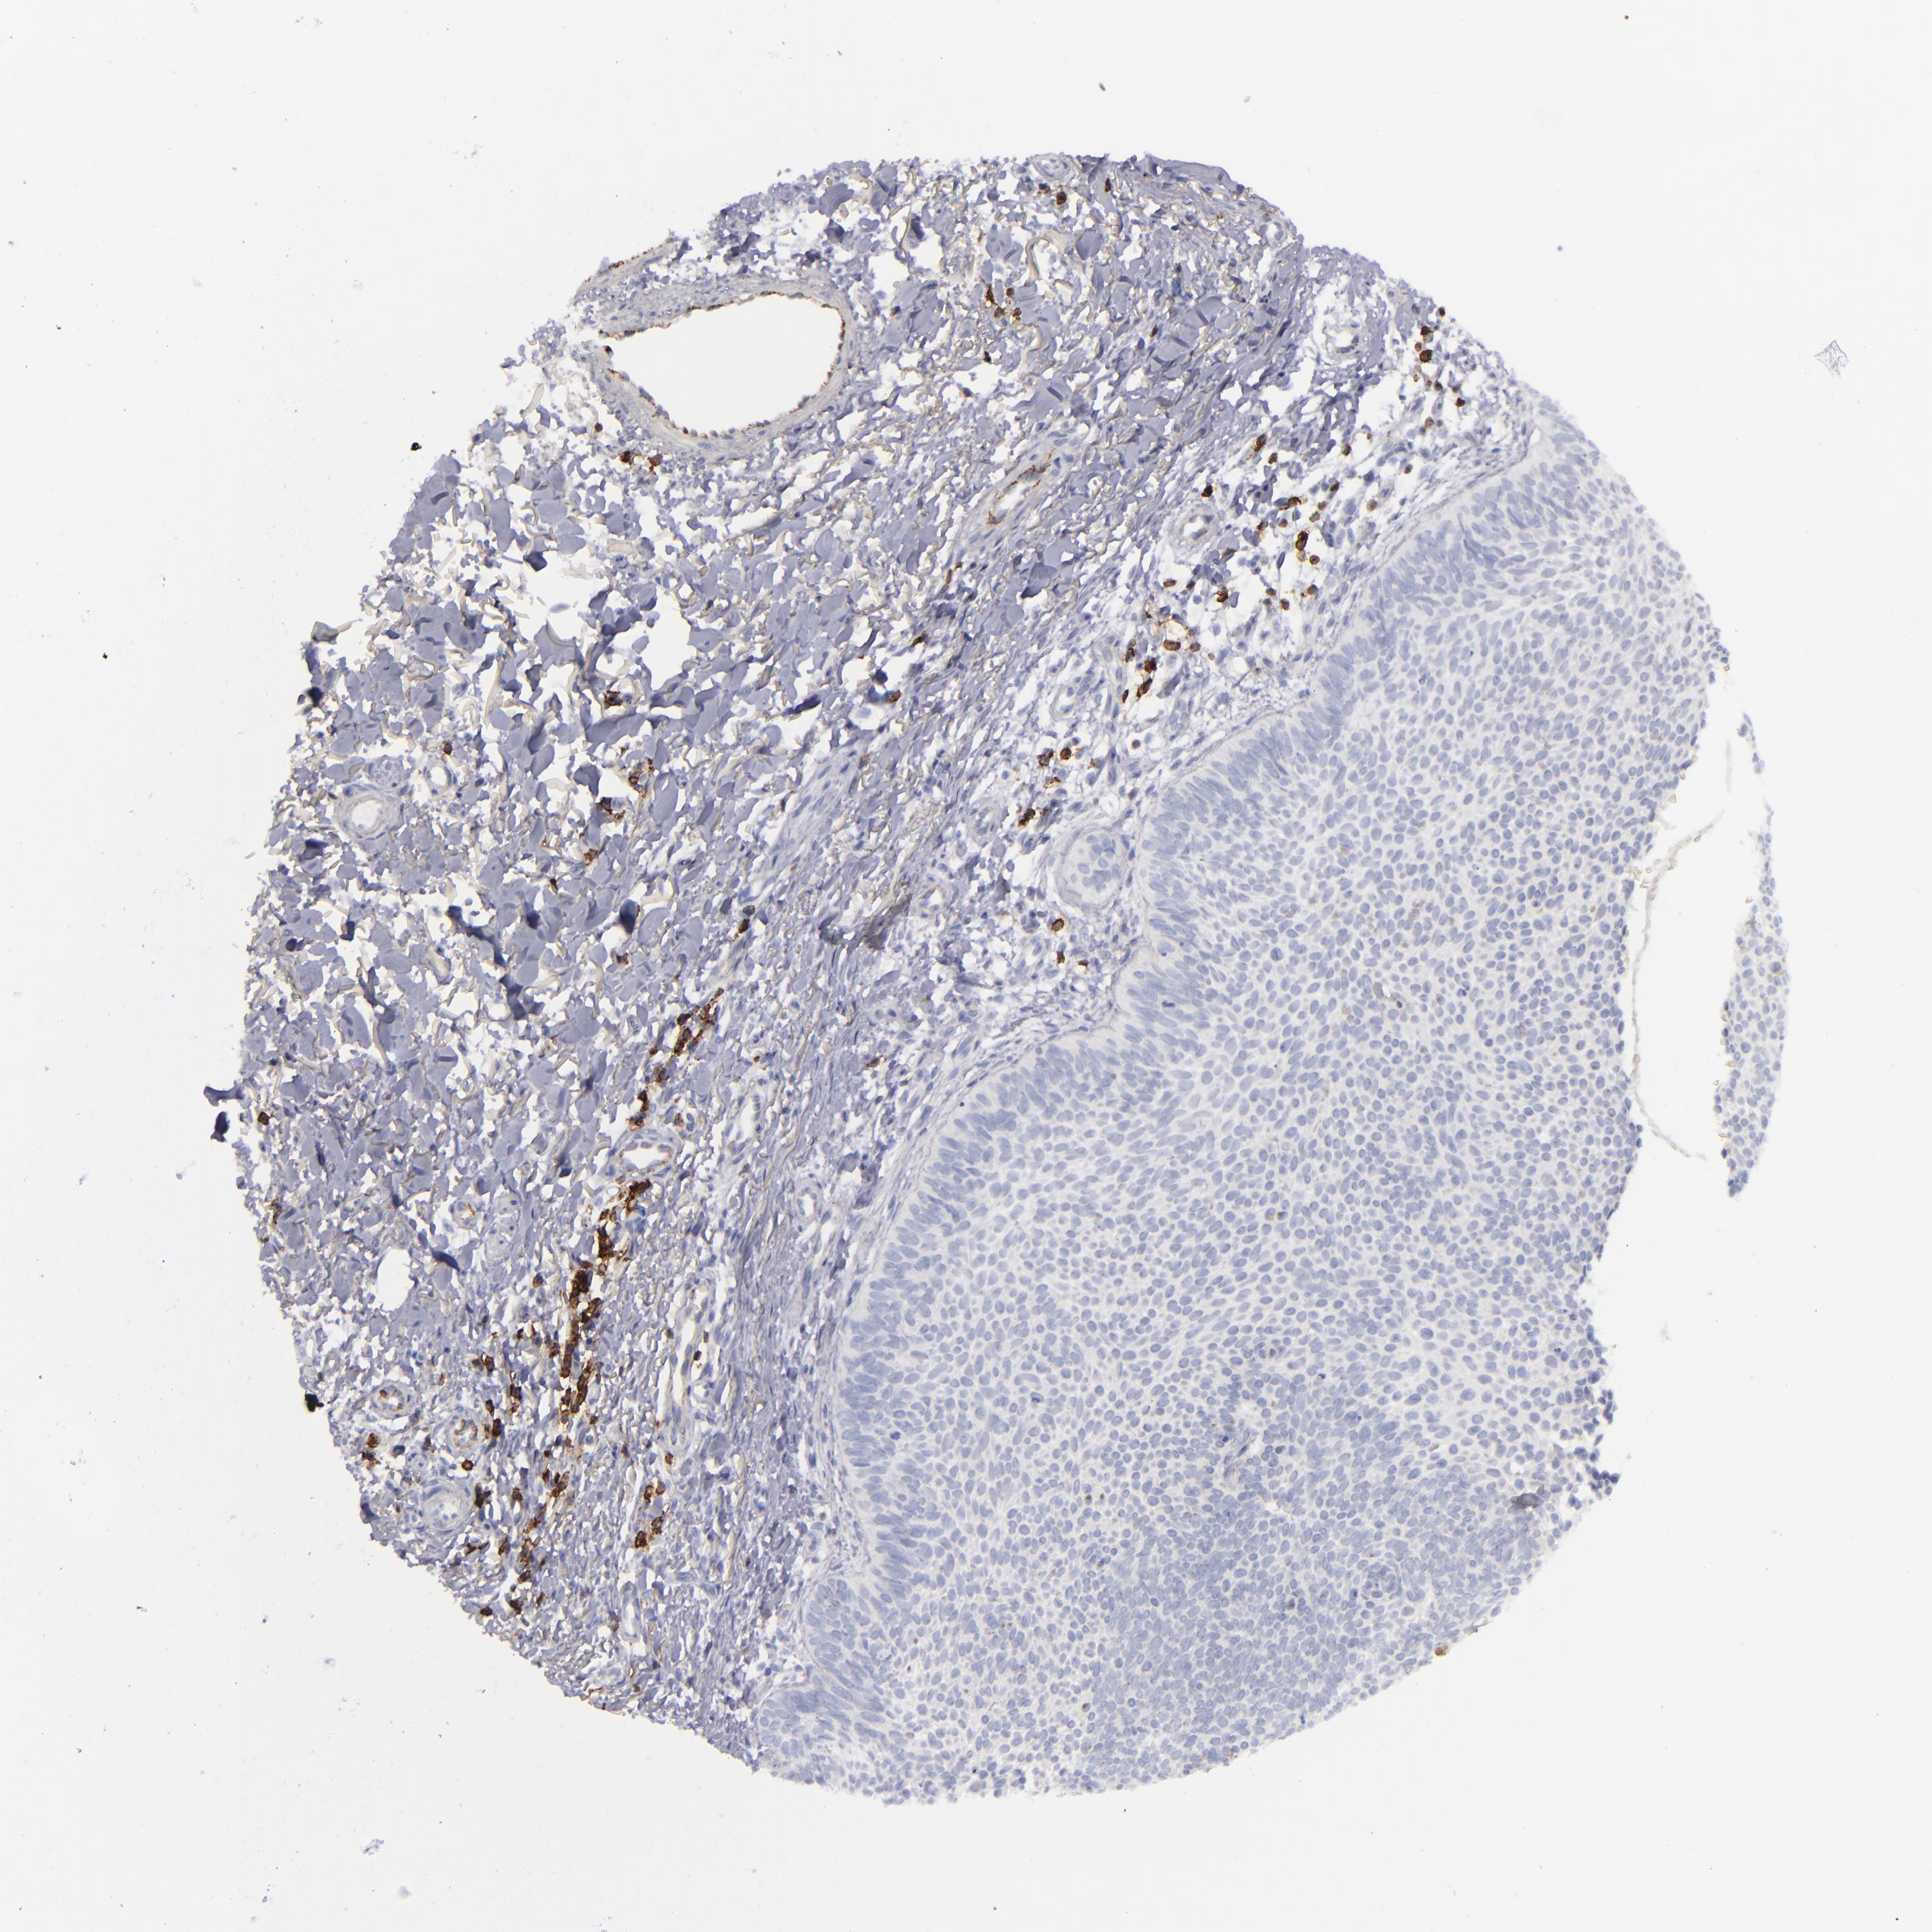

SKIN CANCER - Protein expressioni

A mouse-over function shows sample information and annotation data. Click on an image to view it in a full screen mode. Samples can be filtered based on level of antibody staining by selecting one or several of the following categories: high, medium, low and not detected. The assay and annotation is described here.

Each image is clickable and will lead to virtual microscopy that enables deeper exploration of all samples and also displays staining intensity scores, fraction scores and subcellular localization as well as patient and tissue information for each sample.

Antibody CAB080304

Squamous cell carcinoma, NOS